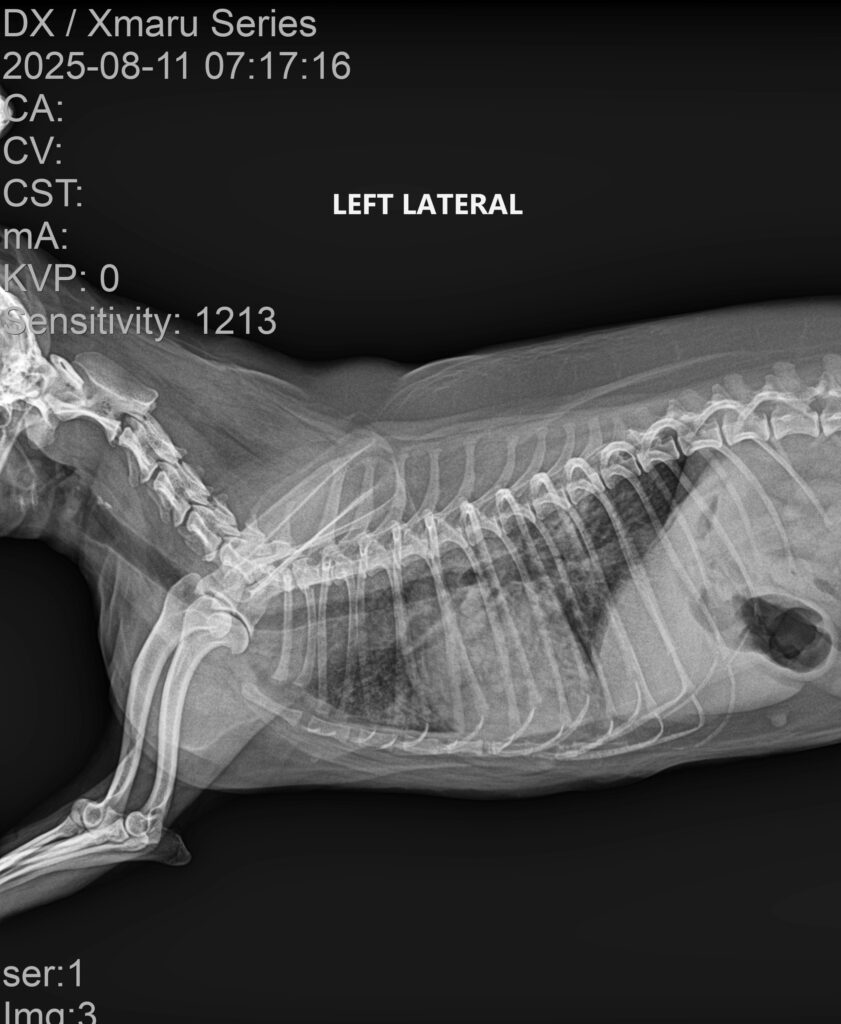

강아지의 호흡이 갑자기 빨라지거나 얕고 가쁜 호흡을 반복한다면 단순 감기나 피로로 넘기기 쉽지만, 실제로는 폐렴(Pneumonia) 과 같은 중증 호흡기 질환일 가능성이 높습니다. 오늘은 산책 이후 갑작스럽게 호흡곤란이 발생한 13살 강아지의 사례를 통해, 폐렴의 진단 과정과 치료, 그리고 회복까지의 경과를 소개드리겠습니다. 강아지 폐렴 치료 케이스 이번 환자는 13살 믹스견의 중성화한 암컷 강아지로, 보호자님께서는 “3일 전 산책 […]